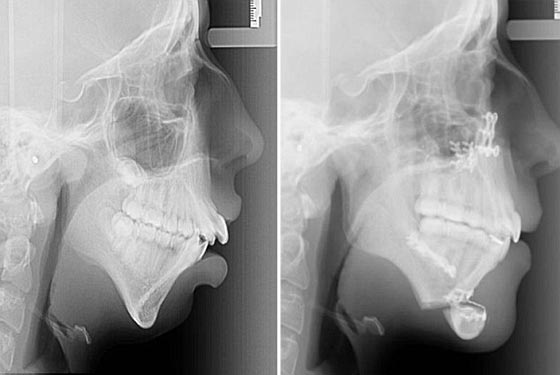

غيرت عملية جراحية حياة فتاة تبلغ من العمر 20 عامًا محولة شكلها إلى الأفضل. وكشفت الصور التي التقطت لفتاة تدعى "إيلى جونز" قبل وبعد إجرائها عملية جراحية تجميلية للأسنان عن تحول كبير في الشكل الخارجى لوجهها.

توقفت أسنان "جونز" من "ويلز" عن النمو منذ كان عمرها ثماني سنوات لتوقف نمو الفك وأصبحت تعانى من تشوه في الفك وهو ما اكتشفت أنها مصابة به منذ ولادتها عندما لجأت لعمل تقويم لأسنانها في سن الرابعة عشر، ولكن بعد عملية التجميل أصبحت أكثر ثقة في نفسها. خضعت "جونز" لأأول عملية جراحية وهى في سن السادسة عشرة، حيث كانت تتناول السوائل فقط ولم تكن تستطيع التحدث بشكل صحيح لكن مع مرور الوقت أصبحت تتحدث بشكل أفضل.